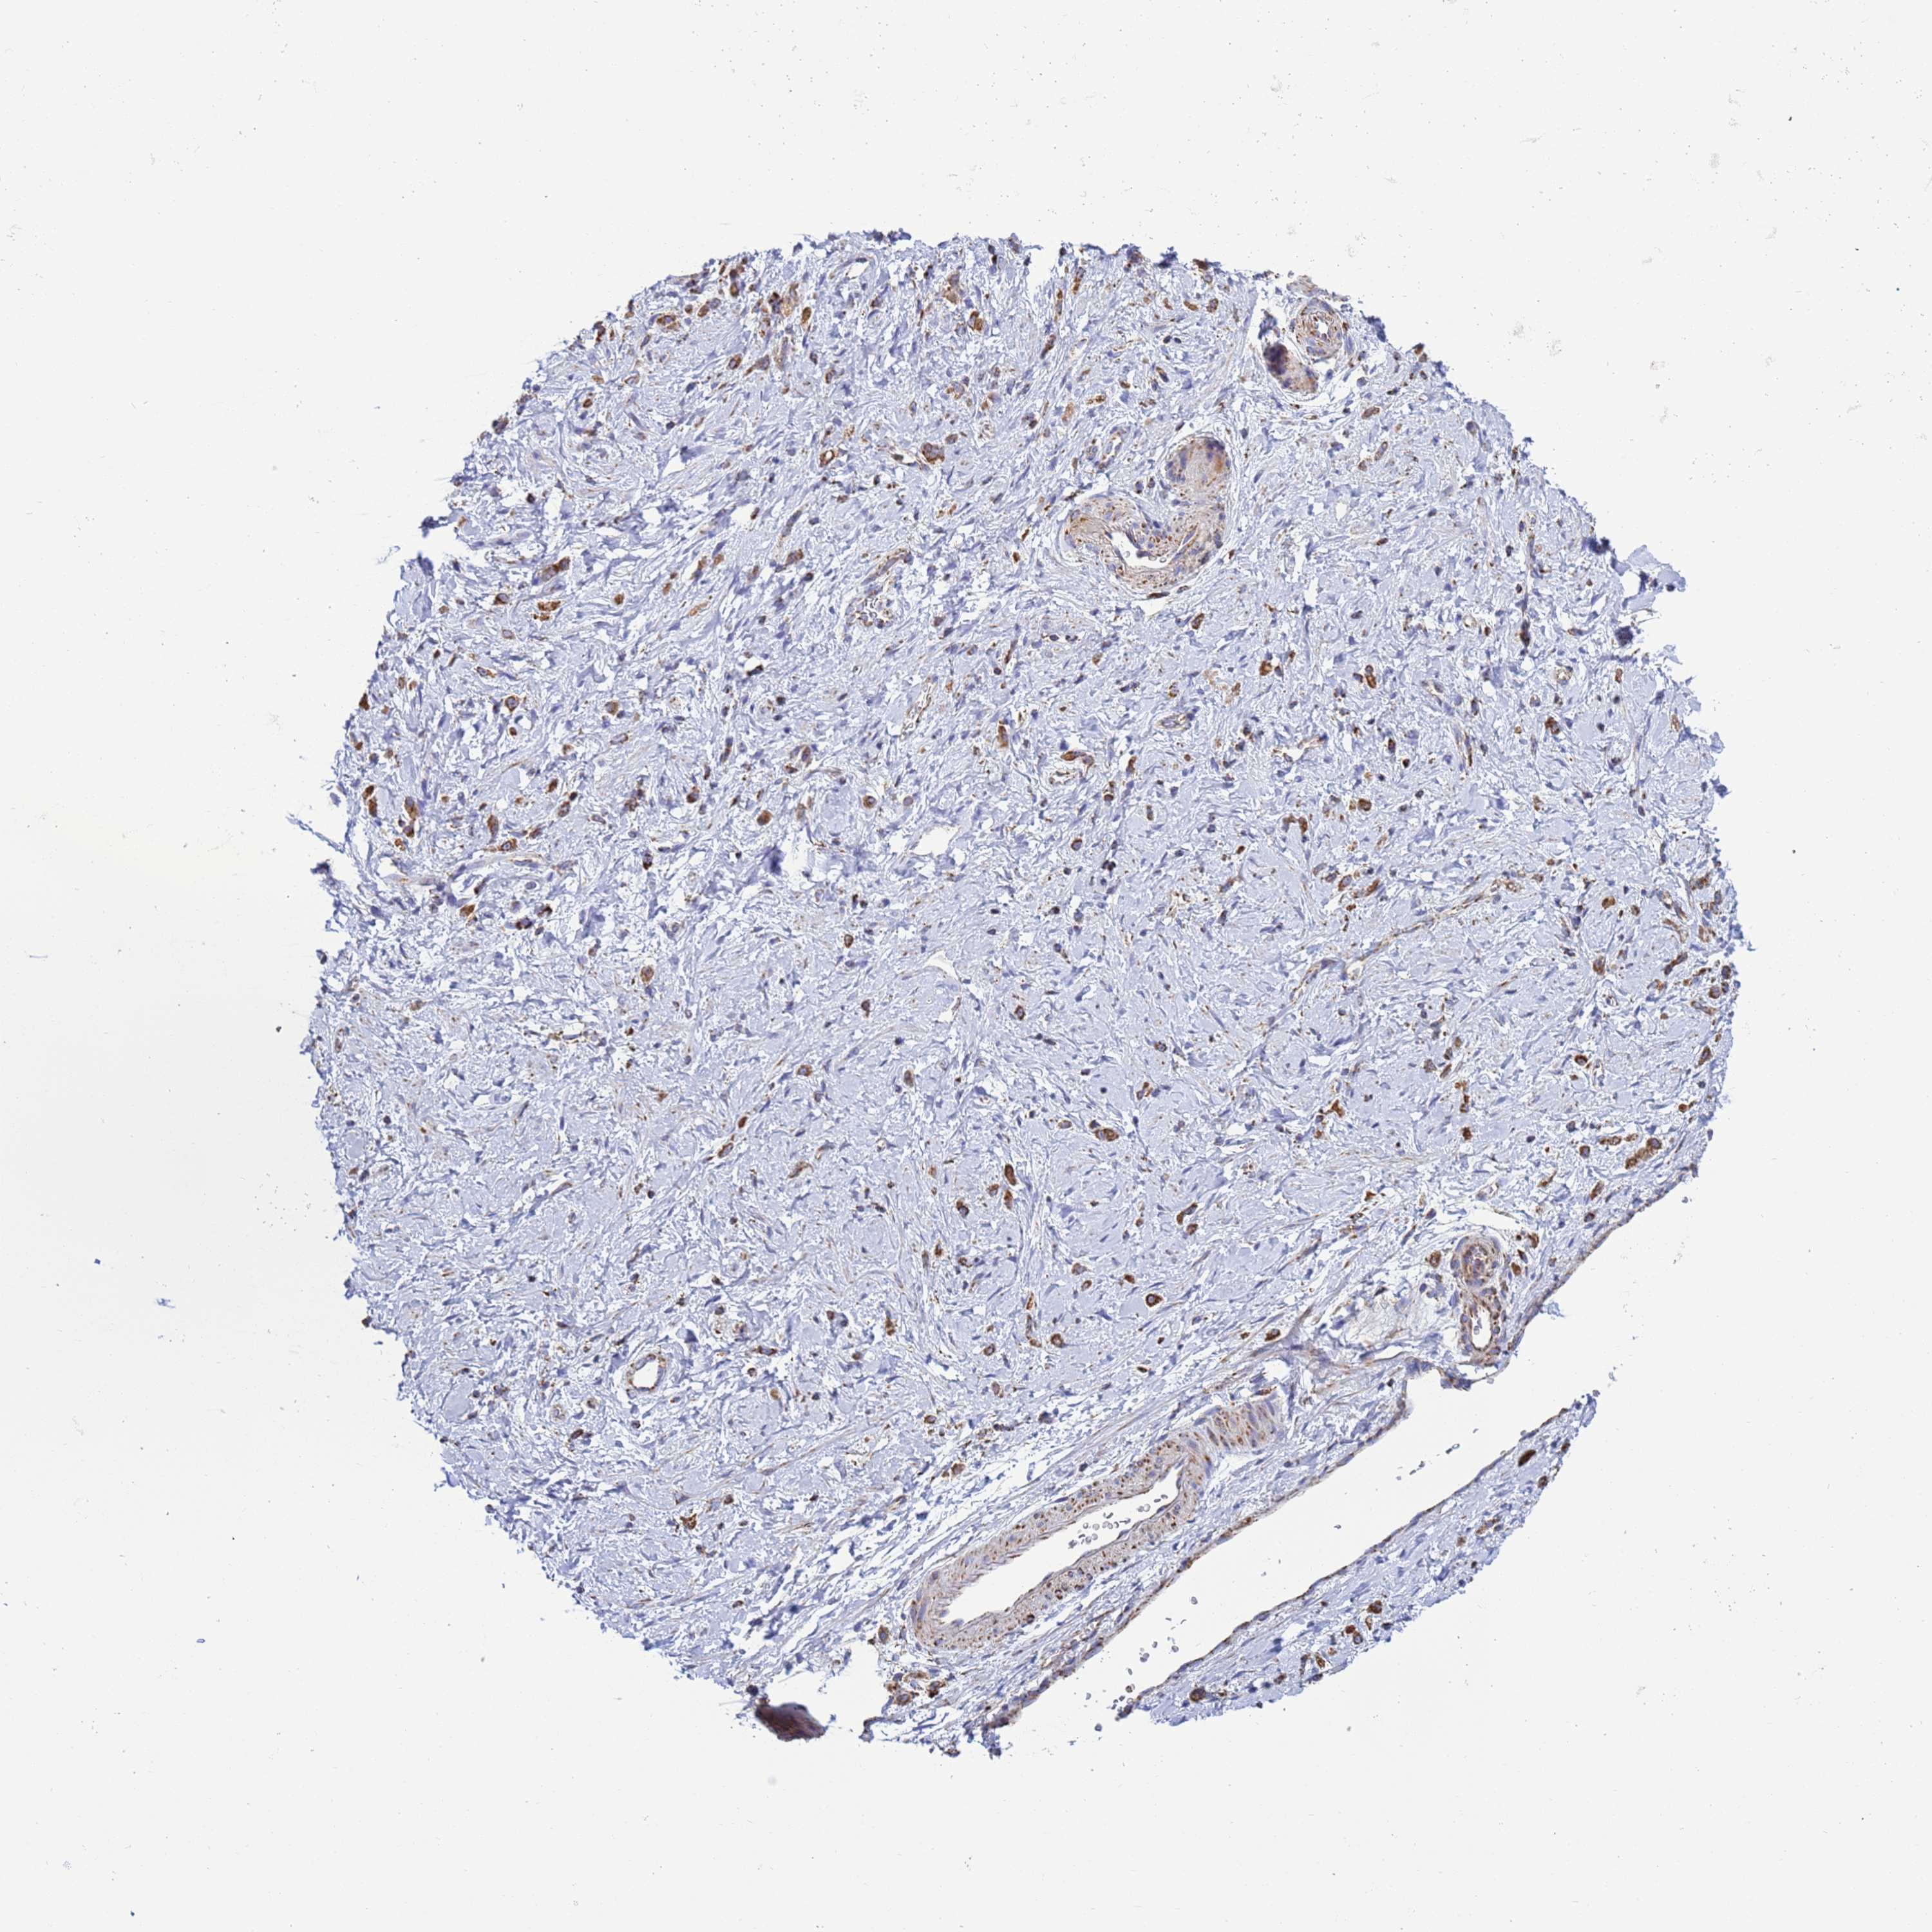

STOMACH CANCER - Protein expressioni

A mouse-over function shows sample information and annotation data. Click on an image to view it in a full screen mode. Samples can be filtered based on level of antibody staining by selecting one or several of the following categories: high, medium, low and not detected. The assay and annotation is described here.

Note that samples used for immunohistochemistry by the Human Protein Atlas do not correspond to samples in the TCGA dataset.

Antibody stainingi

Antibody staining in the annotated cell types in the current human tissue is reported as not detected, low, medium, or high, based on conventional immunohistochemistry profiling in selected tissues. This score is based on the combination of the staining intensity and fraction of stained cells.

Each image is clickable and will lead to virtual microscopy that enables deeper exploration of all samples and also displays staining intensity scores, fraction scores and subcellular localization as well as patient and tissue information for each sample.

Antibody HPA042945

Staining

High

Medium

Low

Not detected

Intensity

Strong

Moderate

Weak

Negative

Quantity

>75%

75%-25%

<25%

None

Location

Nuclear

Cytoplasmic/membranous

Cytoplasmic/membranous,nuclear

Adenocarcinoma, NOS